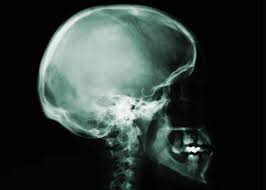

Greetings readers. I have spent the past few days to-and-froing from my son in the hospital undergoing a corrective surgery related to pectus carinatum, and full-family summer and researching the pros and cons of PDA (patron- or demand-driven acquisitions). I am very happy to say that after a nearly 5-hour surgery, in which we allowed “experts” to cut our son’s chest nipple to nipple, lay back the muscle, chip-scrape “excise” the cartilage out of his ribcage, crack his sternum, reshape him and insert a flexible metal bar…he is recovering smashingly, already walking about, playing card-games, and humorously retorting. This is the first “major” operation, injury, break, accident or otherwise that has occurred to my genetic offspring, and, although I’ve endured much trauma with the injuries and surgeries of my spouse, I was unsure what to anticipate going through in allowing invasive slicings and breakings to my precious son’s body.